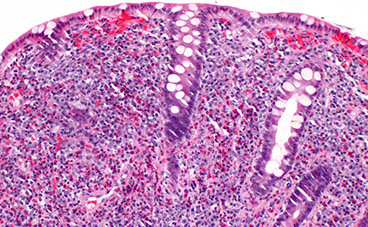

Appendicitis

MC surgical emergency in pediatric pts, although can affect all age groups

- appendiceal obstruction MC caused by lymphoid hyperplasia or fecolith

Sx: initial diffuse umbilical pain then becomes localized to RLQ (McBurney's point) 2/2 different internal structures being irritated

- may perforate

(+) Rovsing, Psoas and Obturator signs

DDx: Diverticulitis (elderly); ectopic pregnancy (get B-hCG to r/o)

Dx: clinical, US/CT confirms

Tx: laparoscopic appendectomy on day of dx